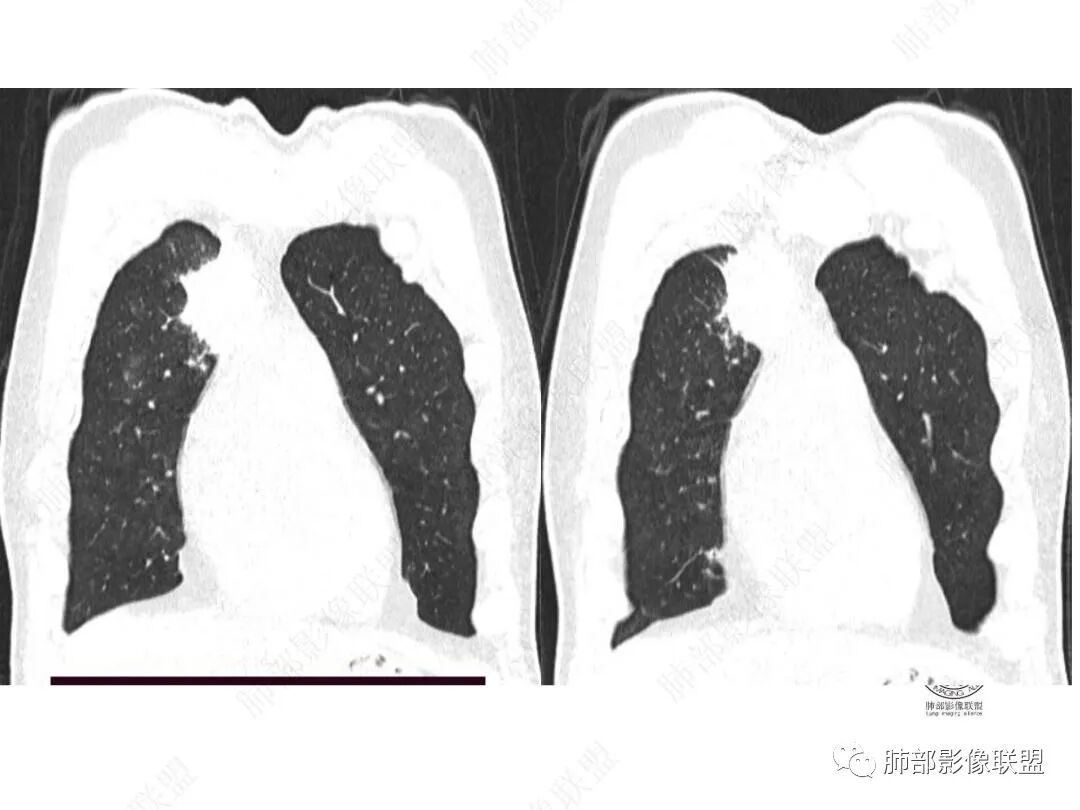

平扫图像

右上叶前段胸膜下新发病灶;纵隔淋巴结较前增大

边缘平直,有锯齿状影

2.右肺上叶纵隔旁新发实性密度病灶,密度均匀,轻度强化,未见空洞、液化坏死及钙化,血管穿行自如,支气管进入后狭窄截止。灶周磨玻璃影边界不清,病灶未见明显分叶毛刺,平直、轻度收缩、周围偶见结节影,但未见树芽征。注意纵隔胸膜侵入或突入比较明确。纵隔淋巴结轻度增大。